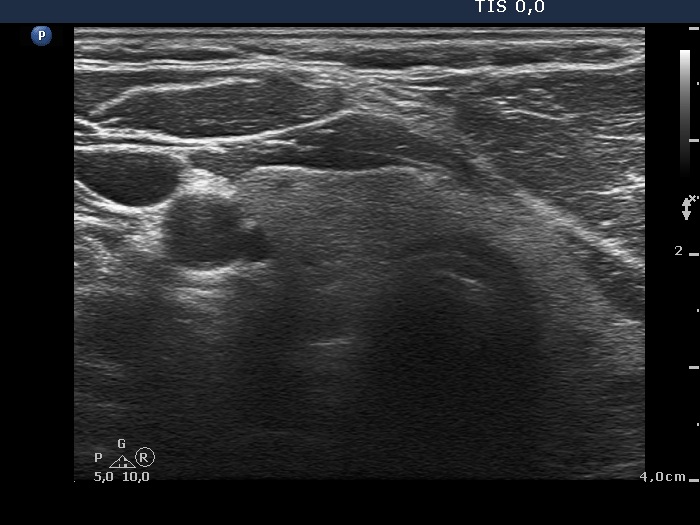

Ultrasonography: the thyroids were echonormal and contained no discrete lesion. According to the palpable mass a large, moderately hypoechogenic lesion was found with pronounced fibrosis. The lesion presented a type 1 vascular pattern.

Diagnosis: lipoma in the neck.